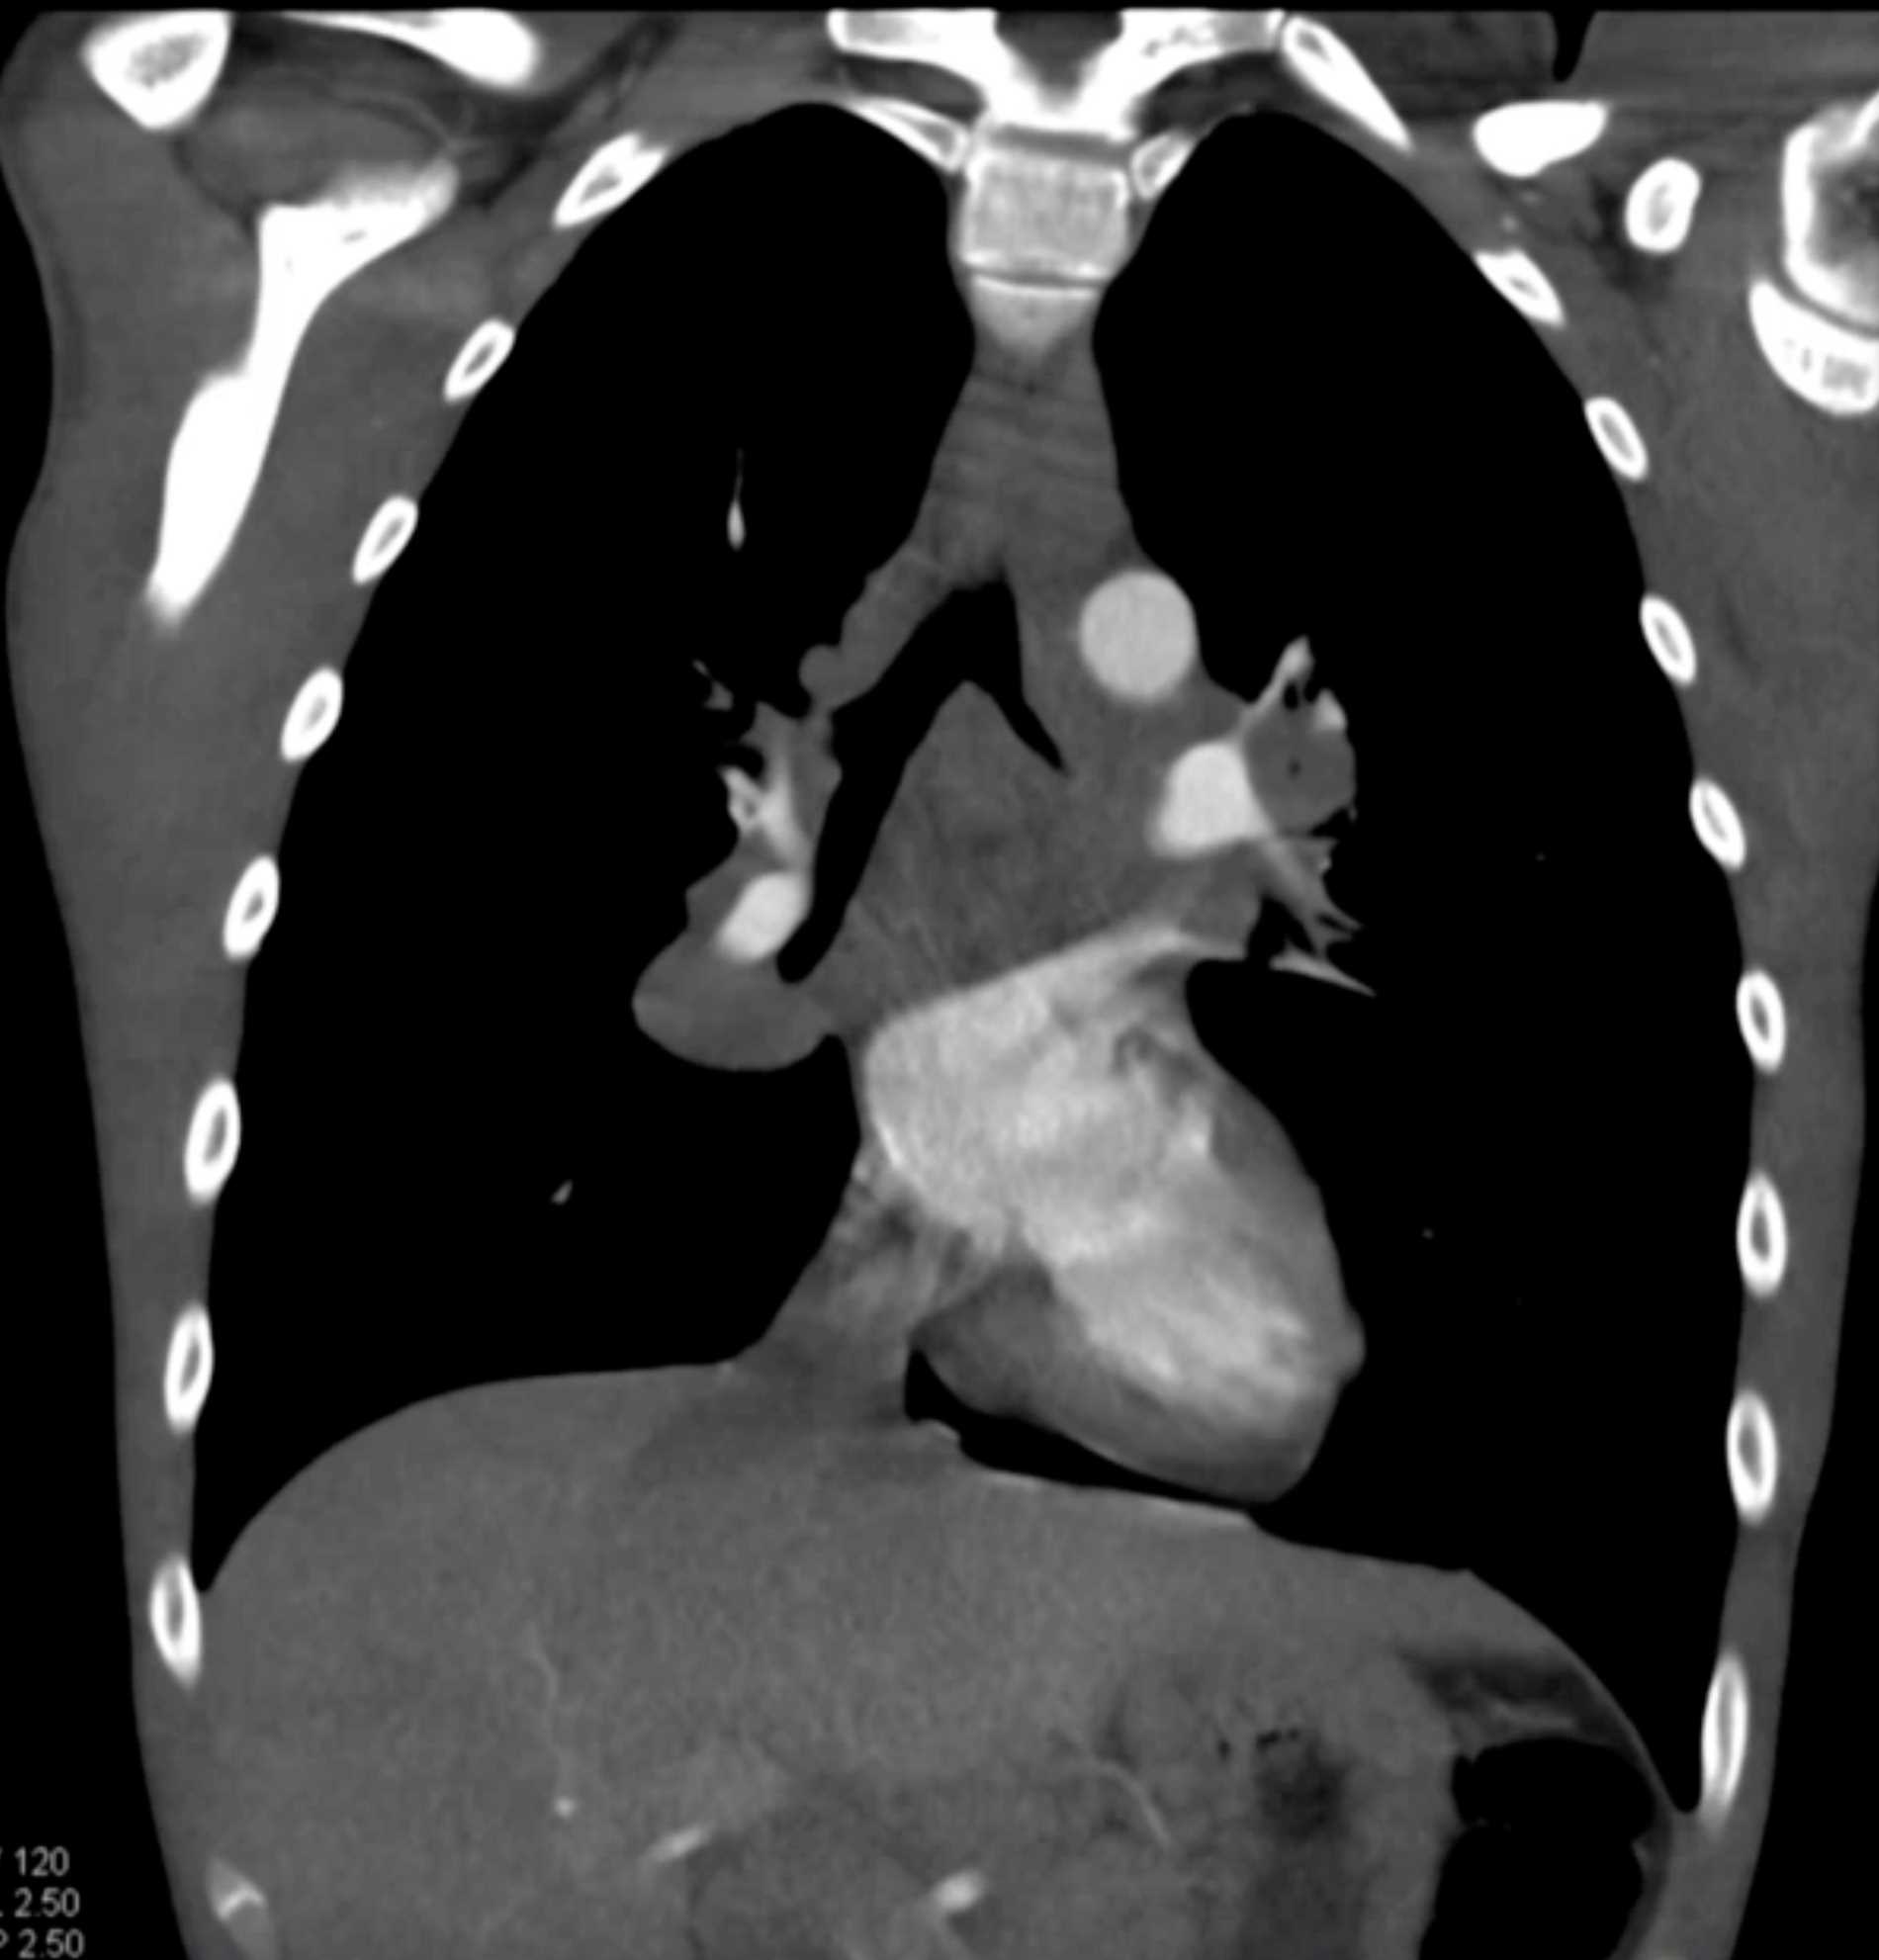

Large Cell Lymphoma